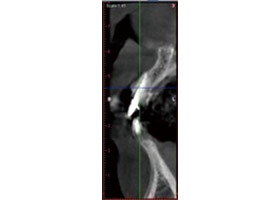

病患植牙前,拍攝3D立體斷層掃描。

當日立即模擬出最適宜的植牙位置。